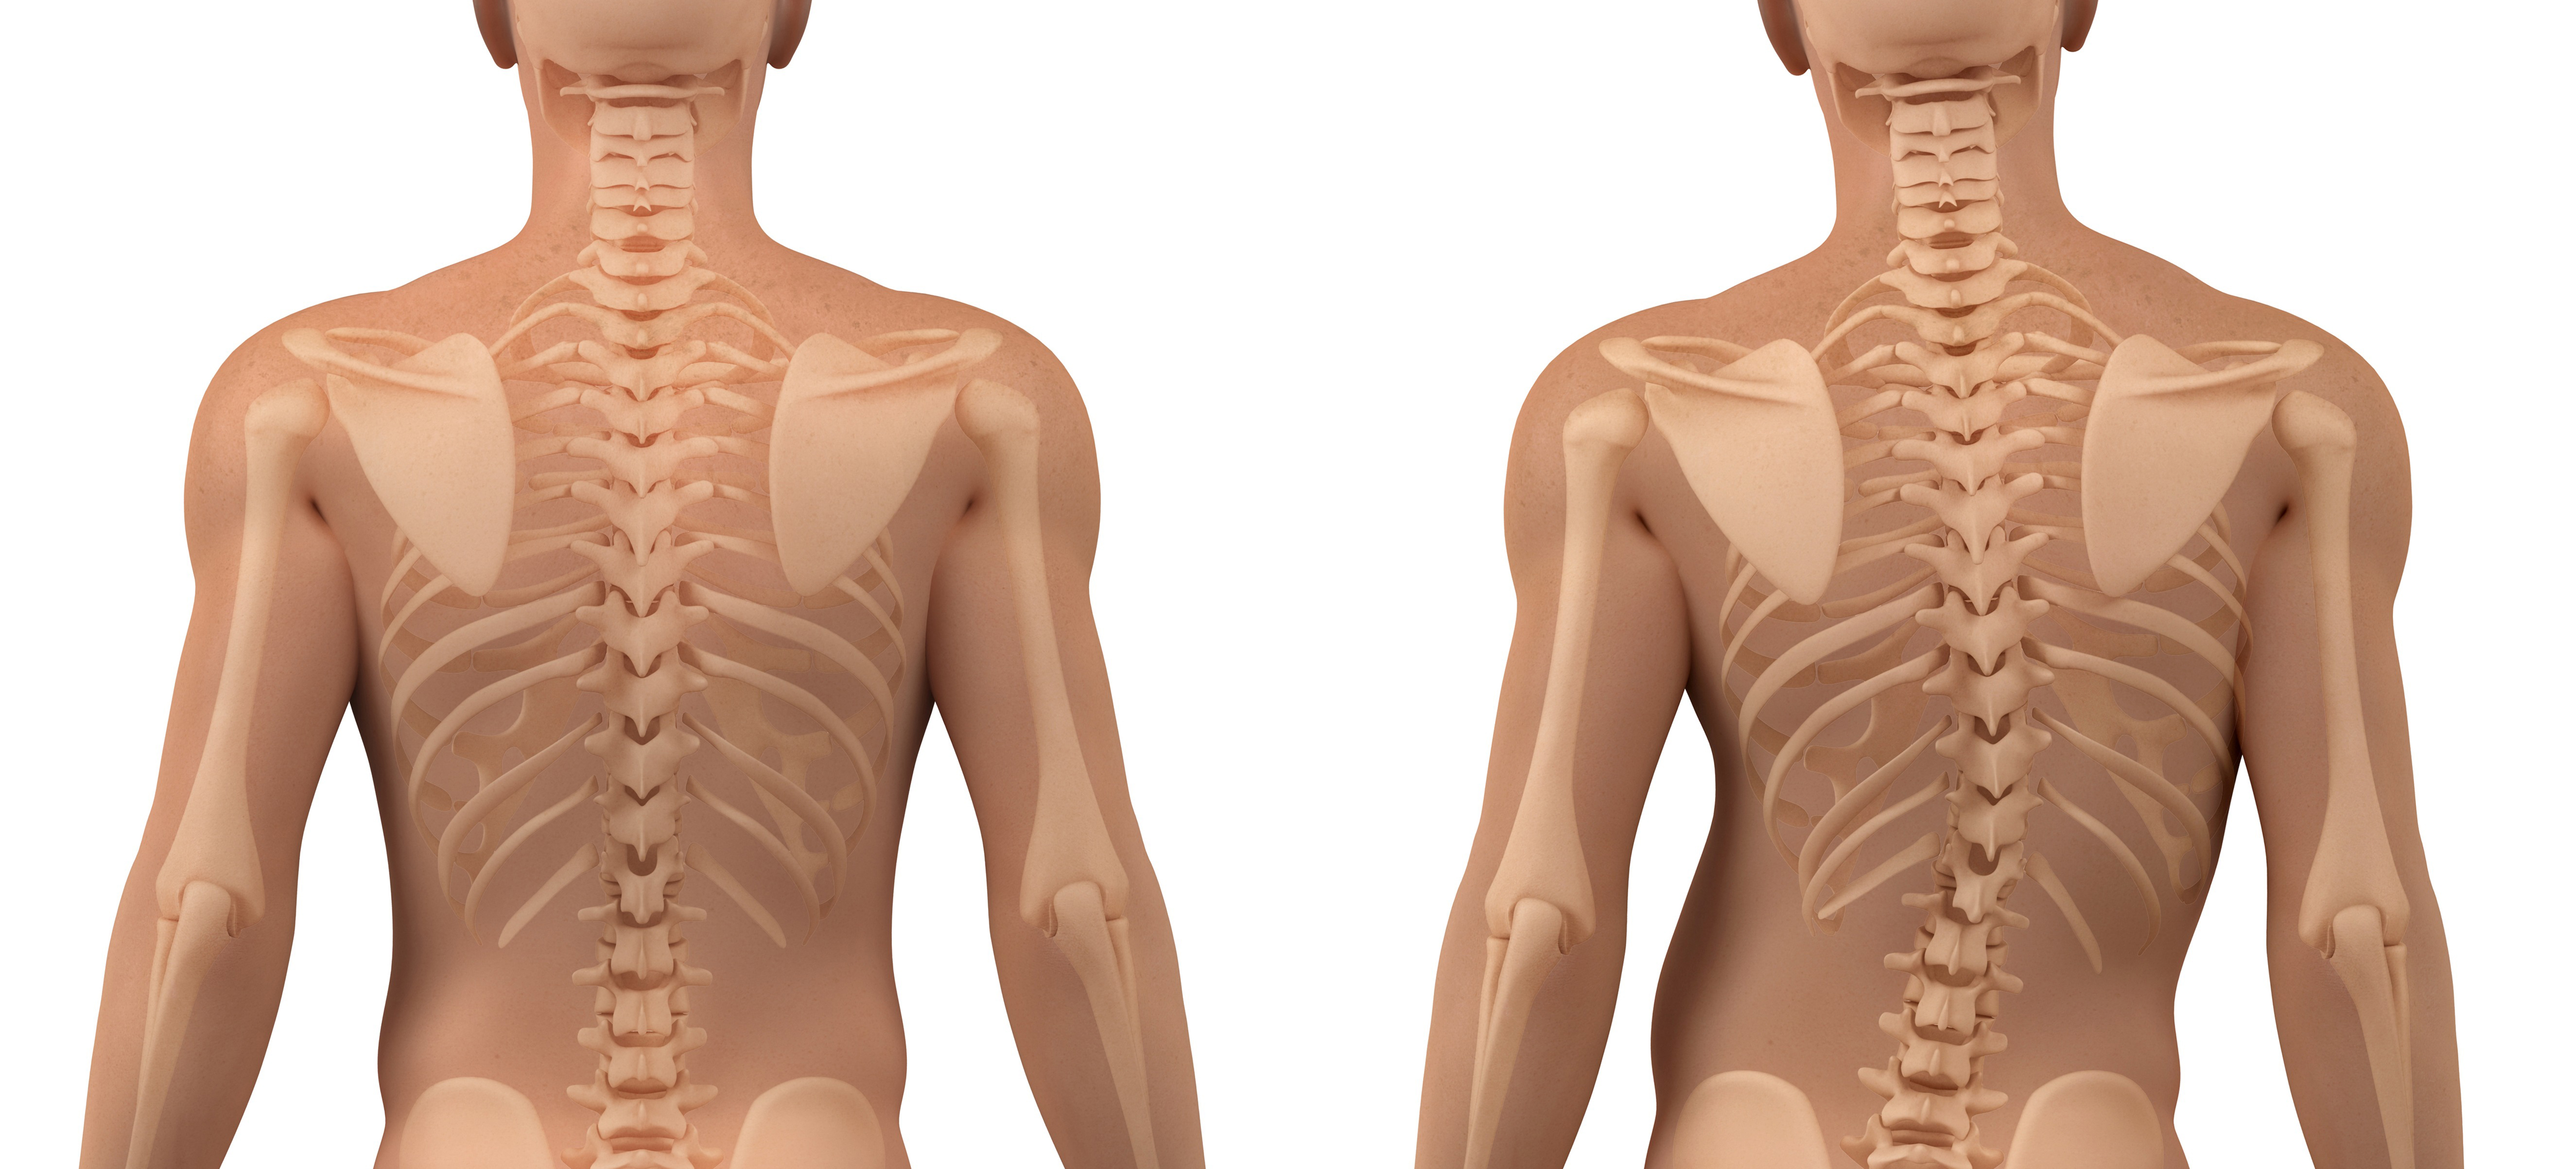

척추측만증의 자가진단법

양쪽 어깨의 높이가 비대칭이다.

서 있는 자세에서 비대칭이 보이거나 한쪽 날갯죽지 뼈가 더 튀어나와 보인다.

허리를 구부린 채 뒤에서 보면 한쪽 등이 더 튀어나와 있다.

허리선이 수평이 아니다.

다리 길이 차이나 골반의 비대칭이 있다. 한쪽 신발이 더 닳는다.

몸이 어느 한 쪽으로 기울어져 있다.